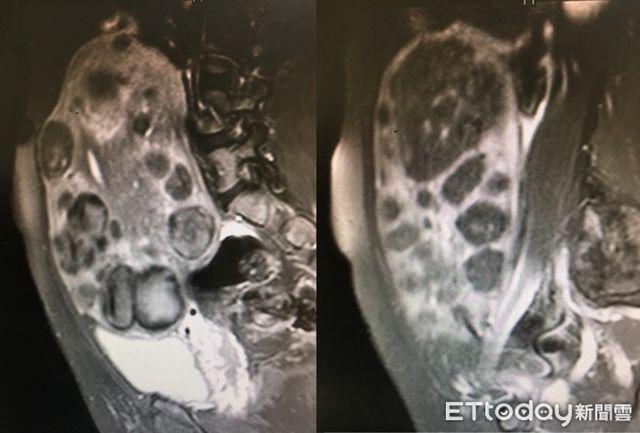

Bác sĩ Trịnh Thừa Kiệt, Giám đốc điều hành của Trung tâm điều trị Hải Phù Đao, thuộc Bệnh viện Bác Nhân Đài Bắc. Đồng thời ông cũng là giáo sư Phụ sản của Đại học y Cao Hùng. Trong cuộc phỏng vấn với Ettoday, bác sĩ Trịnh đã chia sẻ về trường hợp người phụ nữ 48 tuổi – cô Vương, được chẩn đoán có hơn 100 khối u lớn nhỏ ở tử cung, trong đó khối u lớn nhất là 19cm, khối u nhỏ thứ 2 là 12cm, có 90 khối u có kích thước 2cm.

Bác sĩ Trịnh Thừa Kiệt nói rằng, không chỉ như vậy, bụng của cô Vương cũng vì các khối u phân bố rải rác, khiến tử cung phình to như quả dưa, chèn ép bàng quang. Ban ngày, cứ 1 giờ cô Vương phải đi vệ sinh 1- 2 lần, vào buổi tối mỗi đêm cũng phải thức dậy từ 3 lần trở lên, thời gian dài như vậy, đã ảnh hưởng rất lớn đến chất lượng giấc ngủ của cô Vương. Ngoài ra, phần bụng lớn khiến nhiều người còn hiểu lầm, cho rằng cô Vương đã lớn tuổi còn mang bầu, và thường quan tâm xem “khi nào cô sẽ sinh?”, khiến cô Vương ngày càng mệt mỏi.